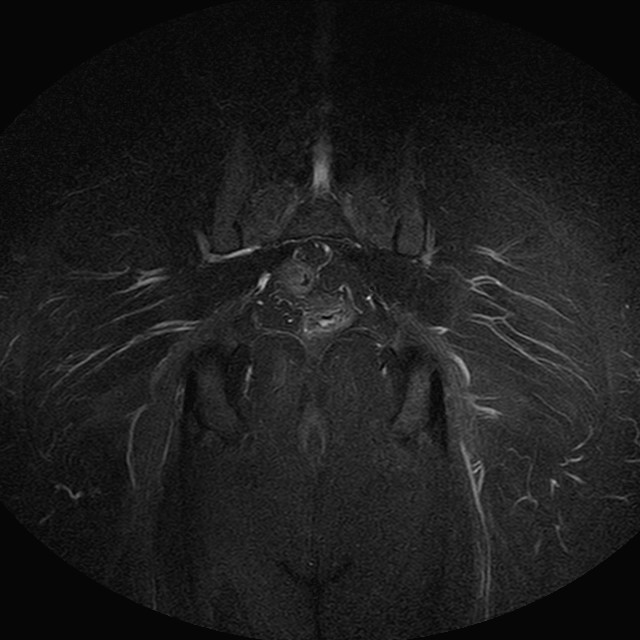

Esami: RMN BACINO

Evidenti e simmetriche alterazioni osteofitosiche in regione coxo femorale con riduzione delle rime articolari. Degenerazione completa del cercine glenoideo. Non attuali segni di versamento articolare. Non segni di edema osseo che escludono attuale algodistrofia od osteonecrosi. Lieve e simmetrica riduzione del trofismo della muscolatura glutea.